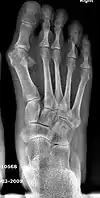

Syndesmosis procedure addresses specifically the two fundamental problems of metatarsus primus varus deformity that gives rise to the bunion deformity. They are leaning and instability of the first metatarsal bone . Syndesmosis procedure uprights the leaning first metatarsal bone with strong binding sutures between it and the second metatarsal bone (Fig. 2) and then also stabilizes it uniquely by creating a fibrous connecting bridge between these two bones (Fig. 3, 4). First metatarsal bone can be readily realigned because by definition of the metatarsus primus varus deformity its first metatarsal is abnormally loose and mobile.

- For severe bunion deformity correction (Fig. 7)